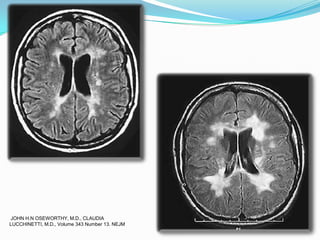

LESIONES AGUDAS

JOHN H.N OSEWORTHY, M.D., CLAUDIA

LUCCHINETTI, M.D., Volume 343 Number 13. NEJM